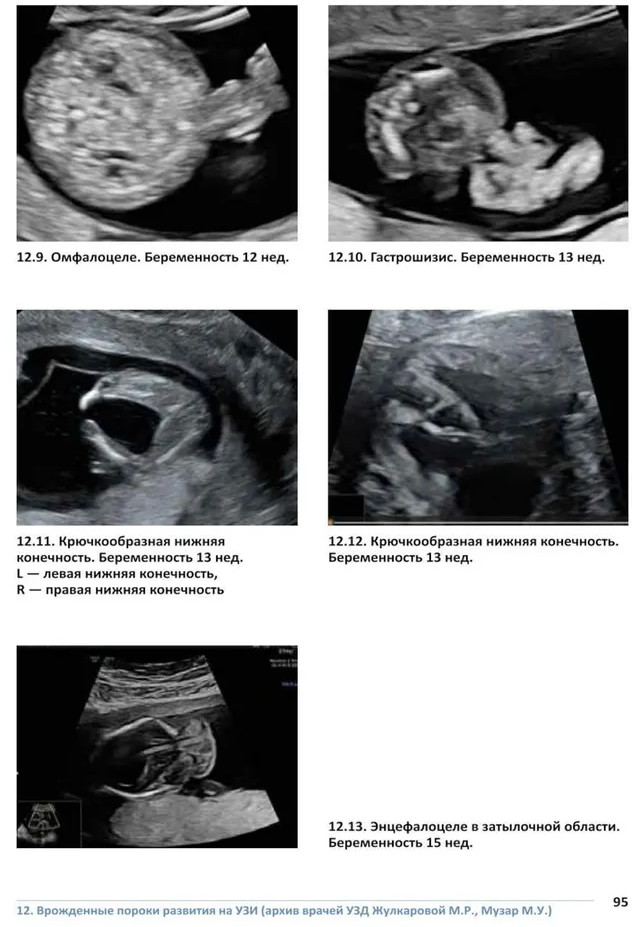

💳 Оплатить за товар можно при получении 🇰🇿 Есть бесплатная доставка по Казахстану от 1 дня 🎁 Копите бонусы с каждой покупки Атлас представляет собой первое в Республике Казахстан учебное пособие для врачей, посвященное врожденным порокам развития плода. Книга начинается с текстового раздела, служащего введением в проблему. Следующая часть издания (непосредственно атлас) представлена сотнями фотографий отдельных пороков развития, подобранными в зависимости от поражения тех или иных органов и систем. Отдельные части атласа содержат ультразвуковые изображения различных пороков развития, а также кариограммы ряда генетических нарушений. Следует особо отметить, что представленный архив фотографий был собран региональными врачами-генетиками. Для врачей-генетиков, цитогенетиков, врачей ультразвуковой диагностики, для специалистов всех направлений службы пренатальной диагностики, по медицине плода, а также специалистов лабораторной генетики. Атлас также представляет интерес для организаторов здравоохранения в области охраны здоровья матери и ребенка. |